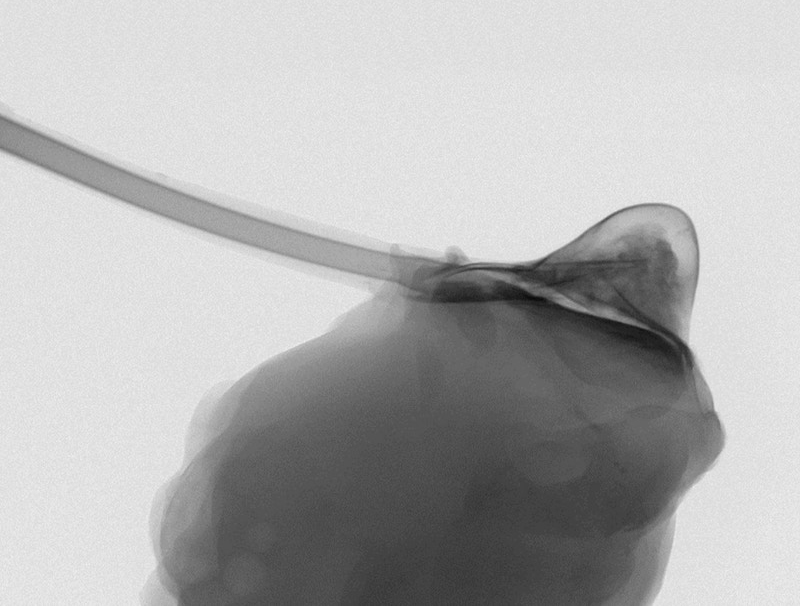

ArrivaTherepi”, un microscopico serbatoio di farmaci che si attacca direttamente al cuore e che può essere riempito dall'esterno in modo semplice grazie a un “tubicino” di collegamento che finisce sotto cute.

Therepi - fatto di un polimero gelatinoso a forma di semisfera con la parte schiacciata che si attacca al cuore - può anche rilasciare cellule per veicolare terapie cellulari che riparano il cuore nelle aree danneggiate da infarto. «Dopo un infarto potremmo usare questo apparecchio per rilasciare terapie preventive contro l'insorgere dell'insufficienza cardiaca», spiega Ellen Roche, coautore del lavoro del MIT, Institute for Medical Engineering & Science.